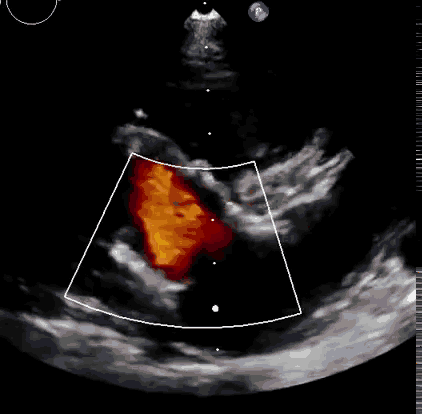

上海中山醫(yī)院葛均波院士、錢(qián)菊英院長(zhǎng)、周達(dá)新教授、潘文志教授、潘翠珍教授、李偉教授共同完成此次臨床前研究。術(shù)后葛均波院士對(duì)Lux-Valve Plus的器械操作性能給予了高度評(píng)價(jià),DSA和超聲影像也顯示出在本次研究中Lux-Valve Plus的安全性和有效性俱佳。

本次臨床前研究經(jīng)右側(cè)頸靜脈置入LuX-Valve Plus輸送系統(tǒng)可調(diào)彎鞘管,在DSA及超聲引導(dǎo)下將人工三尖瓣瓣膜植入到原有三尖瓣位置,利用獨(dú)特的錨定技術(shù)將人工瓣膜支架可靠固定在預(yù)定的位置。

Lux-Valve是全球第一款具有我國(guó)完全自主知識(shí)產(chǎn)權(quán)的經(jīng)導(dǎo)管介入三尖瓣置換系統(tǒng),利用前瓣夾持及室間隔錨定的復(fù)合方式進(jìn)行瓣膜裝置的固定,不依賴瓣環(huán)徑向支撐力,同時(shí)采用自適應(yīng)復(fù)合裙邊材料,有效的貼合密封柔軟的三尖瓣瓣環(huán),針對(duì)于三尖瓣返流的患者有優(yōu)異的療效。Lux-Valve Plus采用全新的經(jīng)血管輸送系統(tǒng),經(jīng)頸靜脈入路創(chuàng)傷更小,可以進(jìn)一步降低手術(shù)風(fēng)險(xiǎn)。相信在后期正式臨床研究開(kāi)展中,Lux-Valve Plus必定會(huì)為更多的三尖瓣反流患者帶來(lái)福音。